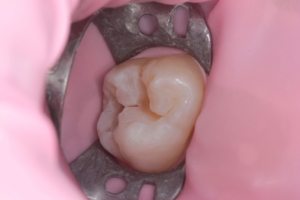

Приклади робіт лікаря-стоматолога

Естетична реставрація. До / після